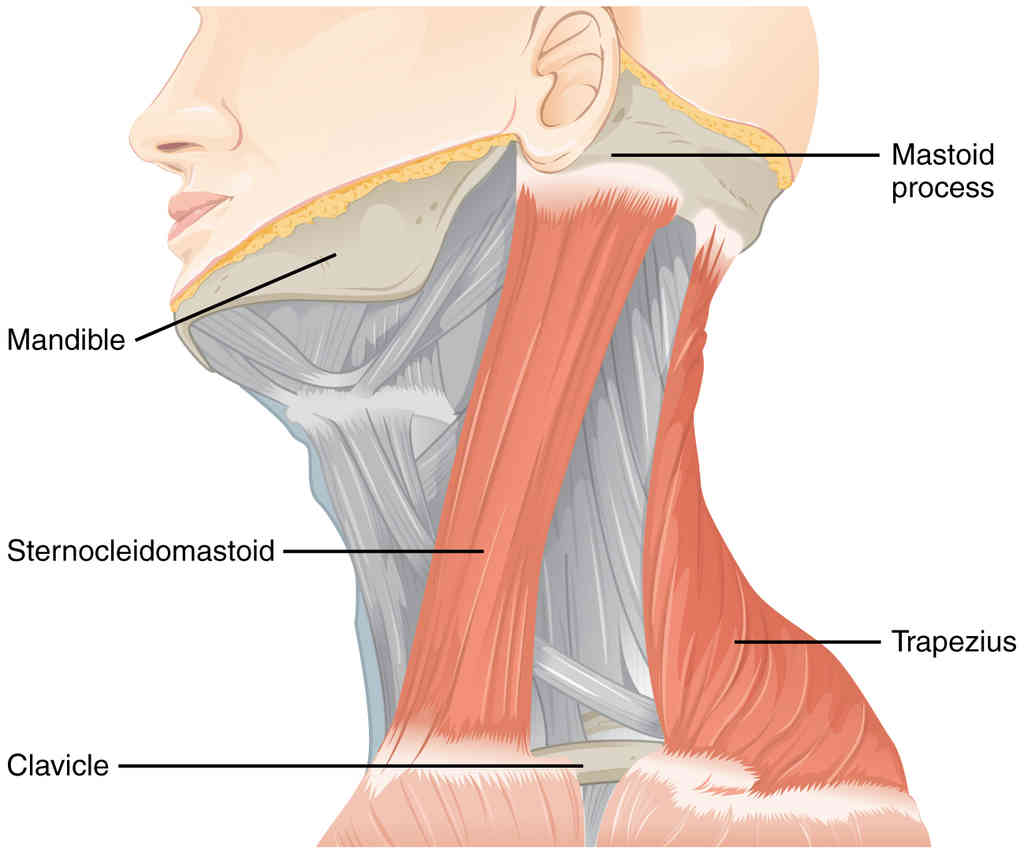

This page is under construction. For now, it is just a resource of the images found in the OpenStax Anatomy and Physiology Handbook. It wil slowly change into a revision tool. Each slide has a number. Use this to refer to the slide. When completed, it will have an unlabelled section, with labelled slides in parallel. On the unlabelled slides, write your answer and use the labelled slide to assess yourself. Keep track by also noting the number on each slide. Improvement at each attempt is important, more so than full marks on a first attempt.